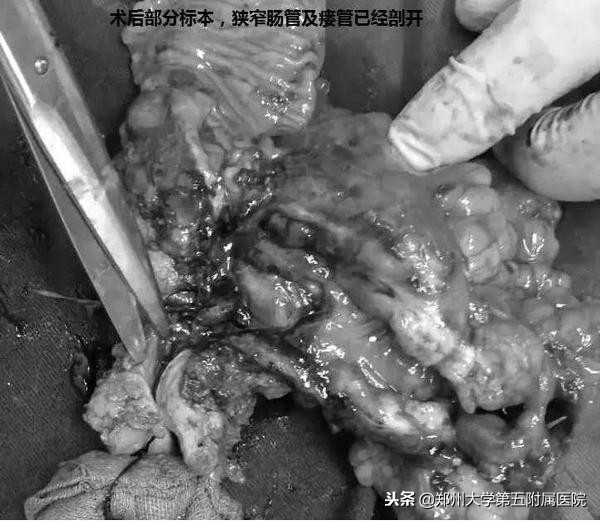

经过充分的术前讨论,制定了详细的手术方案及风险预案,手术如期进行。由崔小兵主任医师主刀,傅聿铭主任医师及吴万庆副主任医师紧密配合,术中仔细分离,顺利切除病变肠管(三处小肠瘘口和原吻合口处肠管)及腹壁三处瘘管,小肠及结肠一期吻合。术后经过肠内肠外营养支持、合理使用抗生素、糖皮质激素合理置换、切口VSD治疗等综合性措施以及护理部精心护理,患者完全康复,腹部切口及3处瘘口愈合良好,进食及大小便正常,恢复顺利,满意回家。